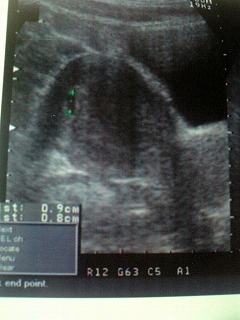

まだまだ小さいサクランボちゃん

来週は、もっと大きくなったサクランボちゃんに会えるといいなぁ